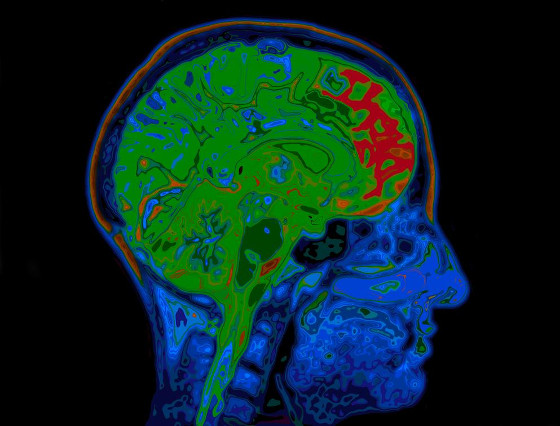

Une étude suggère que le covid-19 est lié à des changements cérébraux semblables à ceux de la maladie d’Alzheimer

Pour certains, ce n’est qu’un reniflement. Mais pour d’autres, le covid-19 peut frapper fort. Dans tous les cas, certaines personnes ayant contracté le covid-19 souffriront d’effets à long terme. C’est ce qu’on appelle le « covid long », et les personnes qui en souffrent sont souvent appelées les « long haulers ». Il y a de fortes chances que vous connaissiez déjà le covid long et que vous en ayez été affecté ou que vous ayez des amis ou de la famille qui le soient. Ce que l’on sait moins, en revanche, c’est que les problèmes neurologiques sont fréquents dans le cas du covid long.

L’inflammation du cerveau, les accidents vasculaires cérébraux, les maux de tête chroniques, les troubles de la conscience, les déficiences cognitives et le « brouillard cérébral » (une expression globale pour décrire un état qui se manifeste généralement par un ralentissement de la pensée, des trous de mémoire et des difficultés de concentration) peuvent tous résulter d’une infection par le virus connu sous le nom de SARS-CoV-2.

Mais si les cliniciens et les patients ont remarqué une myriade de problèmes cérébraux après l’infection, les scientifiques ne savent pas grand-chose sur la manière dont les infections par le SARS-CoV-2 peuvent entraîner une altération des fonctions cérébrales.

Une étude publiée le 3 février dans la revue Alzheimer’s & Dementia met en lumière un mécanisme physiologique potentiel à l’origine des problèmes neurologiques rencontrés par les survivants du covid-19.

La nouvelle étude, intitulée « Alzheimer’s-Like Signaling in Brains of covid-19 Patients », présente des résultats inquiétants.